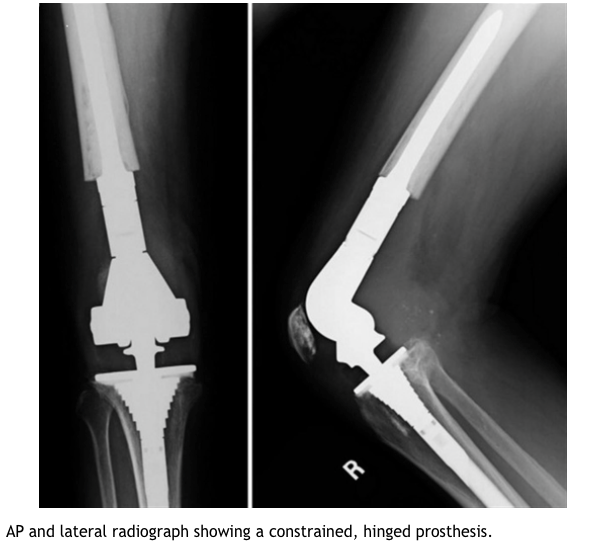

Describe the design of a constrained hinged tkr?

What are the adv and dis of constrained hinged tkr?

Adv

Dis